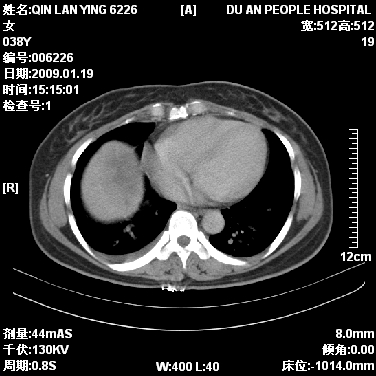

女,38岁,胸疼1个月。wbc:1万4

1)右肺中央型肺癌并右肺上叶阻塞性肺炎、节段性肺不张,纵隔淋巴结转移、右侧胸膜转移、肝脏转移。2)右侧胸腔少量积液。

本病例有几个容易诊断的地方:1、右肺上叶前段支气管闭塞,肺不张。2、淋巴结明显肿大。3、肝脏多个类圆形低密度影呈“牛眼征”改变,高度提示转移。

从影像学角度分析      右肺上叶中央型肺癌,并阻塞性不张、肺炎,纵隔淋巴结、膈顶淋巴结转移。

肝内两个大小不等低密度结节,内可见更低密度影,首先考虑肝内转移瘤,但联想到患者wbc1万4,建议楼主还是做个增强比较明确,除外肝脓肿的可能。